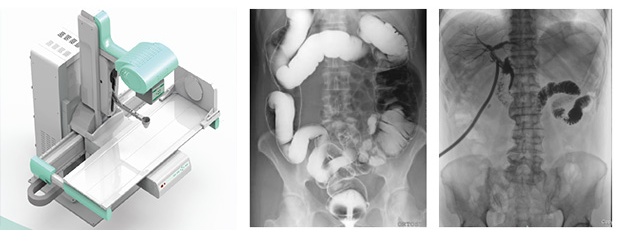

近年来,DR设备正朝着更加准确化、轻便化、智能化和多维化方向发展,出现了多功能动态DR、移动DR、三维化DR产品等等。其中多功能动态DR大大提高了普通放射设备准确诊断的能力,为临床创造了价值。接下来给大家分析下多功能动态DR是如何提高工作效率的。以下是部分体位介绍及解决方案:

在这些对球管中心线和受检部位形成角度有要求的体位的摆位过程中,可以应用多功能动态DR的电动控制摆臂、数字显示角度值和动态透视影像观察功能等特性,使这些体位的摆位更加准确、让医生工作效率更高!如果您想采购普爱医疗的多功能动态DR,或了解产品技术参数,欢迎联系我们。